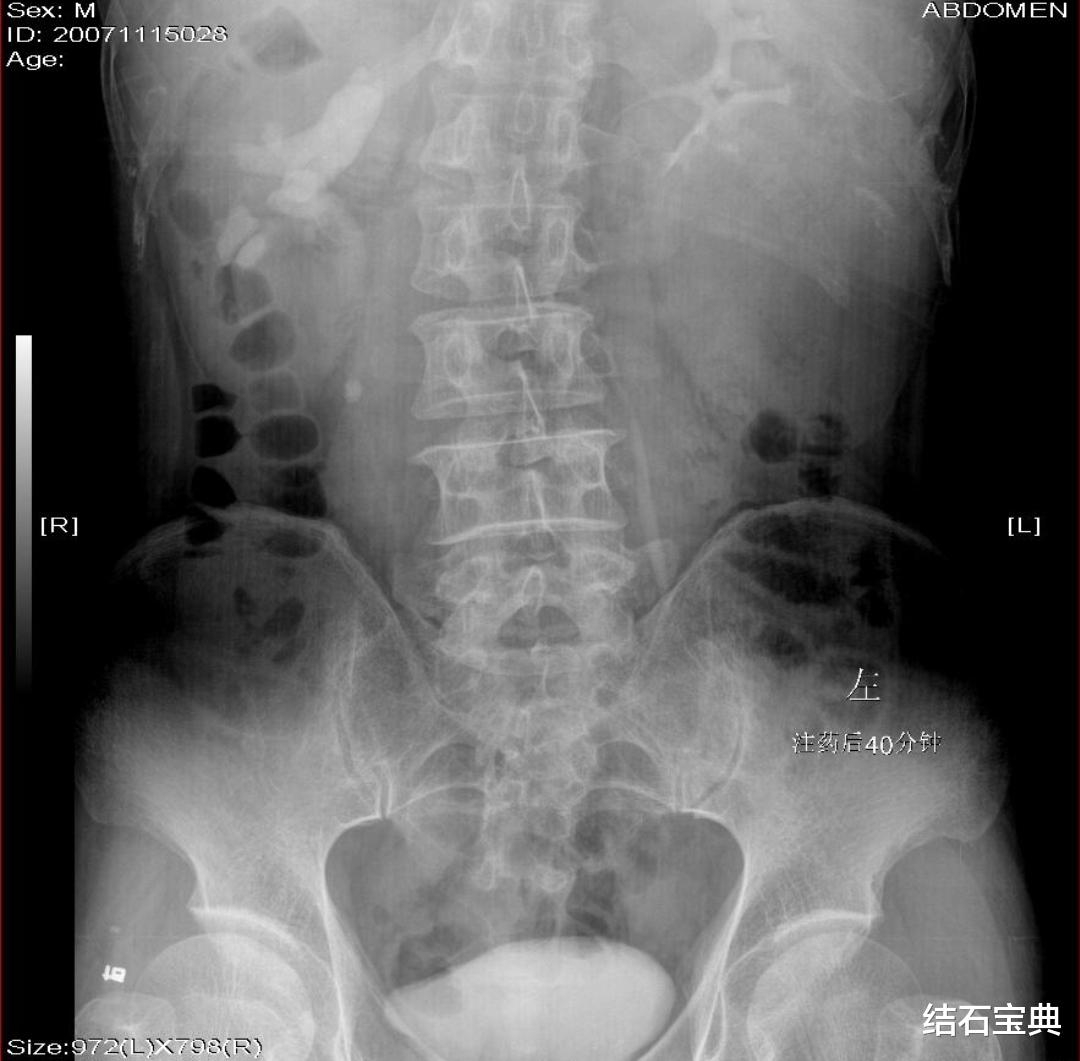

(1)X线片:又称为KUB , 是输尿管结石的初检方法之一 。 约10%的输尿管阴性结石无法被检查发现 。 X线片不适合肥胖、没有充分肠道准备和小结石的患者 。 另外 , X线片无法检查肾积水的严重程度 , 往往无法评估结石梗阻的严重程度和肾实质受损程度 。 X线片有辐射 , 不适合孕妇检查 。 X线平片能清楚地显示结石的大小、位置 , 非常直观 , 且受检查医师的操作水平影响小;故X线片常作为输尿管结石患者的初检方法、体外震波碎石和手术前的定位以及治疗和手术后的随访复查 。